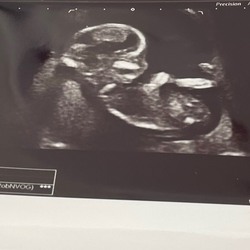

Hai Anne!! Ik woon in Kattenbroek in Amersfoort! Wat leuk! Ik ben momenteel 20 weken en 3 dagen zwanger en ben 23 jaar oud

Hoi! Ik woon ook in Amersfoort. 21 weken zwanger van ons eerste kindje. Lijkt mij leuk om in contact te komen!

Amersfoort hier 👋🏽

19 weken zwanger van onze eerste(jongetje)